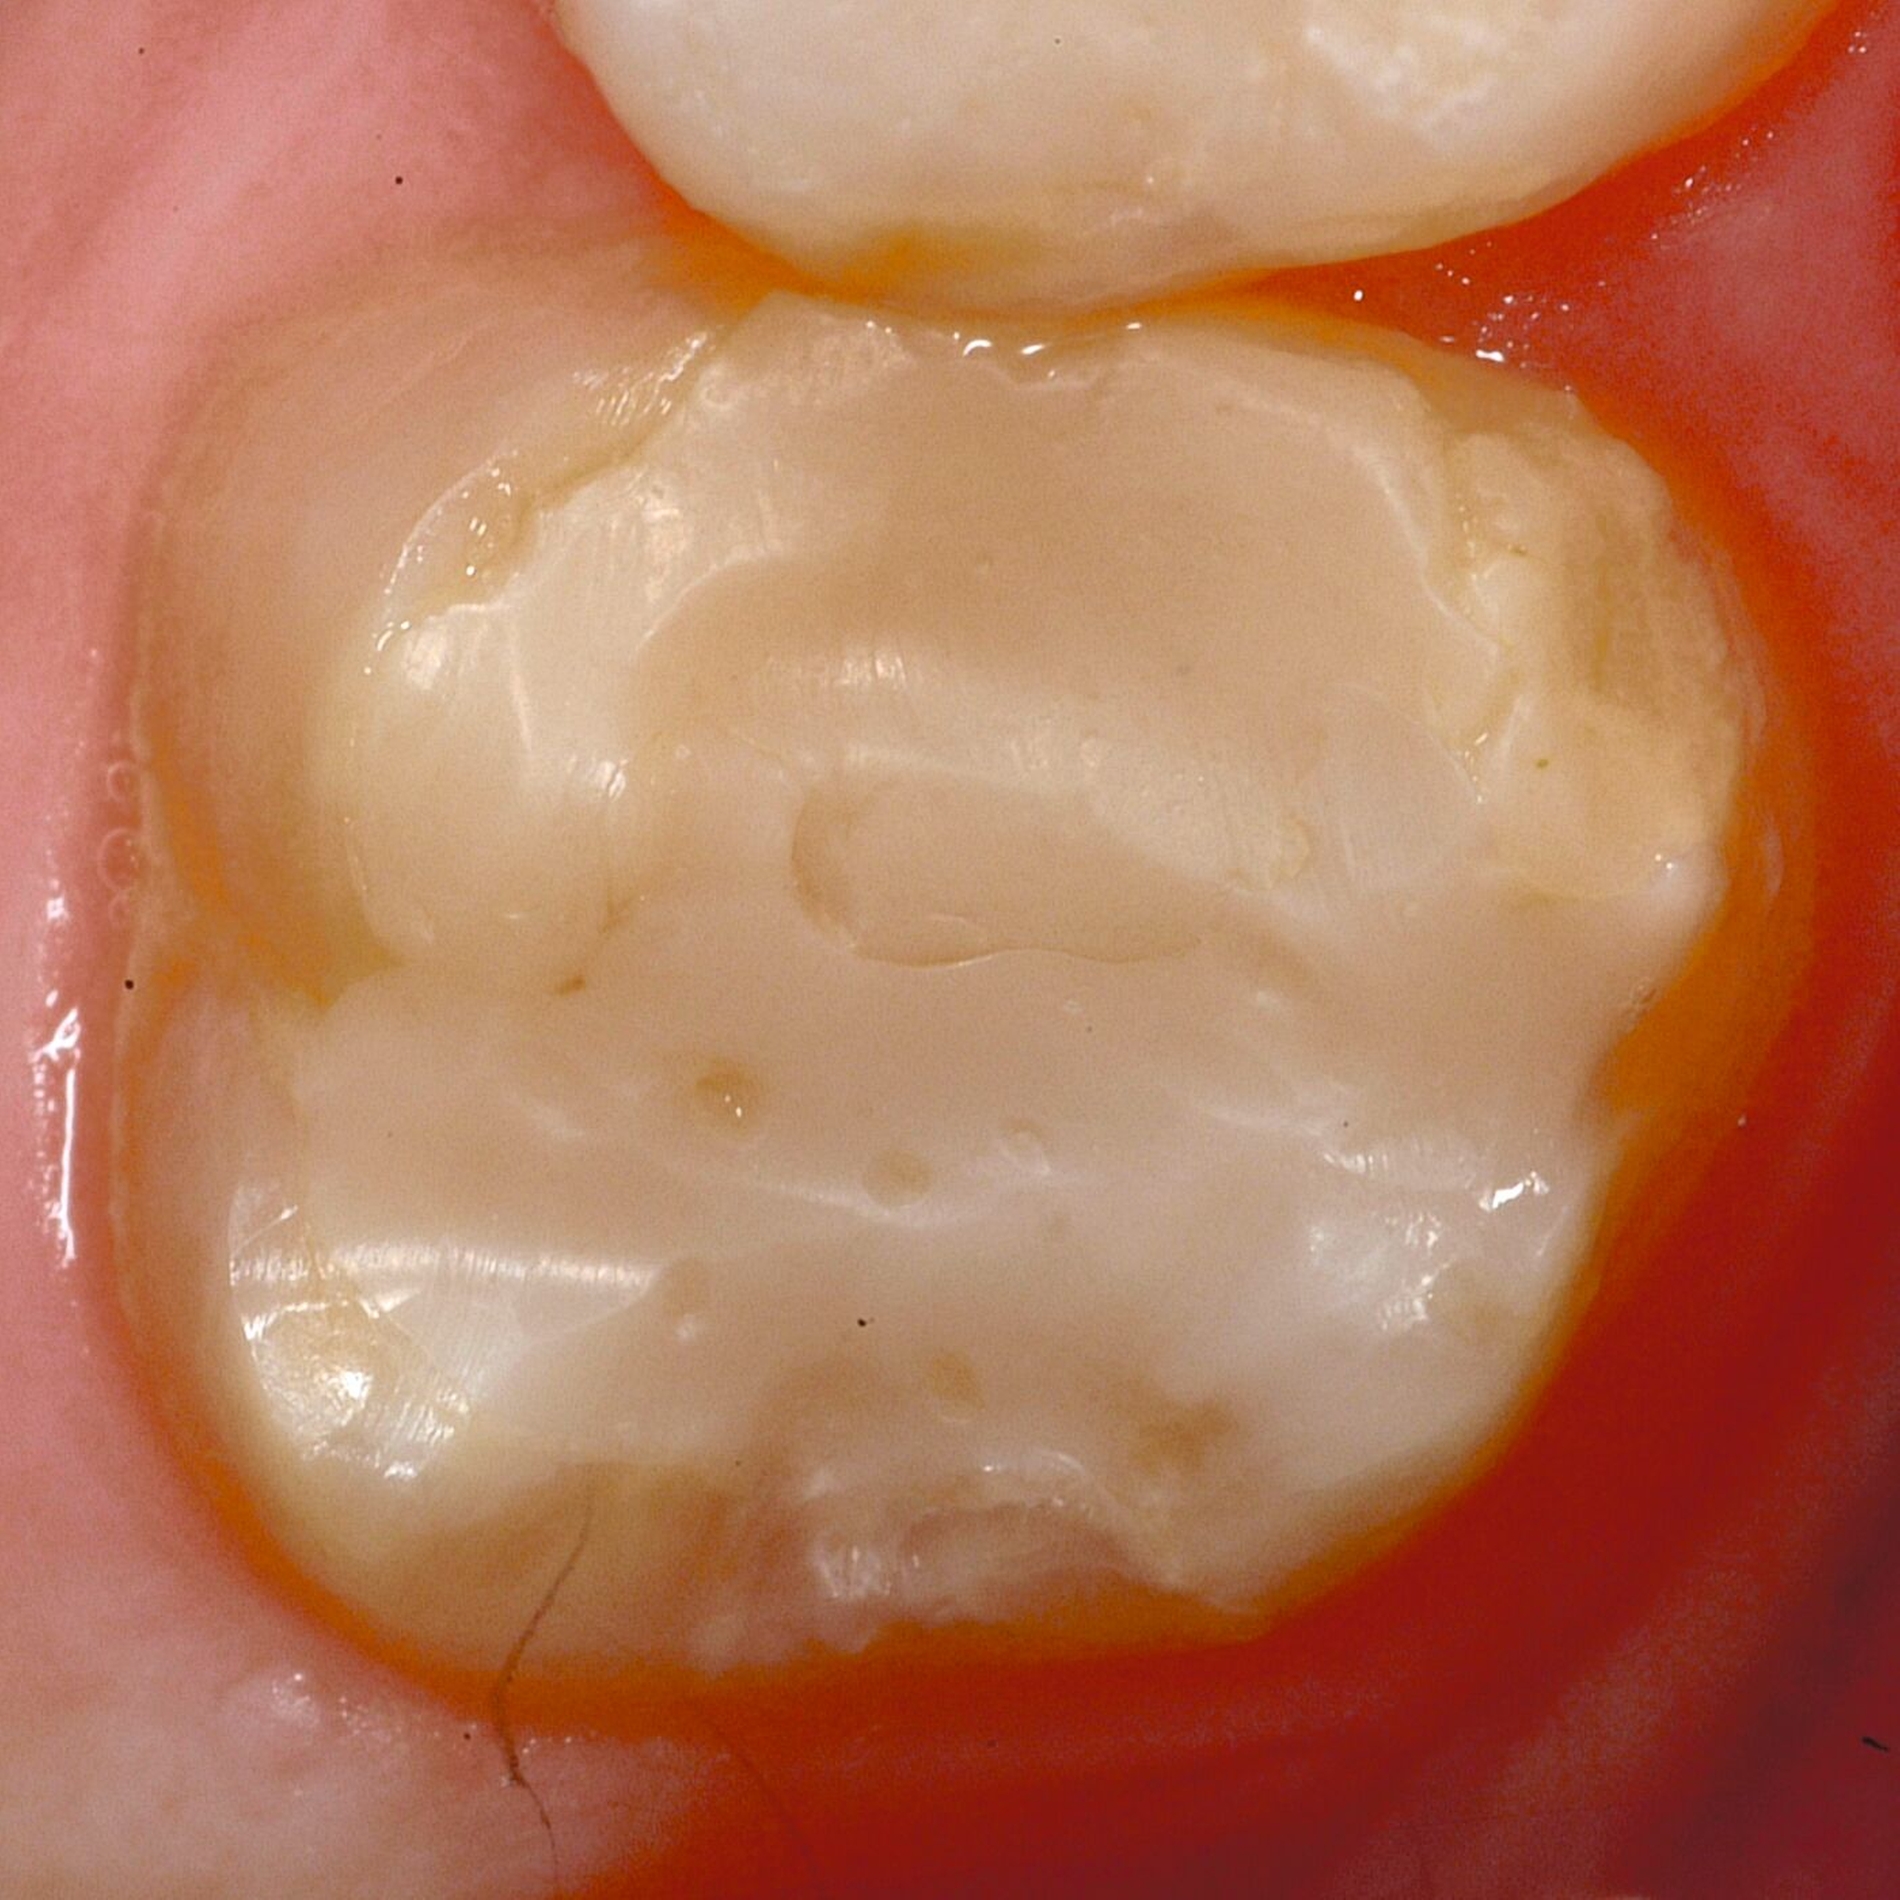

Das klinische Erscheinungsbild an bleibenden Zähnen zeigt typischerweise weißlich-gelbe bis gelblich-braune Opazitäten, die zumindest in einigen Bereichen durch eine scharfe Abgrenzung (engl.:„demarcated opacities“) zum gesunden Zahnschmelz charakterisiert sind (Abbildungen 3 und 4). Die abgegrenzten Hypomineralisationen befinden sich mehrheitlich im Bereich der inzisalen Kronenhälfte unabhängig von dem Auftreten an Front- oder Seitenzähnen. Die Ausprägung am Zahn kann dabei auf einzelne Areale oder Höcker begrenzt sein.

Für die Dokumentation und Klassifikation der MIH wurden verschiedene Systeme vorgeschlagen. Als historisch und veraltet gilt der (modifizierte) DDE-Index. Demgegenüber haben die Kriterien der EAPD – abgegrenzte Opazitäten (Abbildung 3 und 4), Schmelzeinbrüche (Abbildung 5), atypische Restaurationen (Abbildung 6) – mittlerweile die weiteste Verbreitung gefunden. Diese wurden 2003 erstmals zur Beschreibung der MIH auf empirischer Basis publiziert [Weerheijm et al., 2003] und den Jahren 2010 und 2022 im Rahmen der damaligen MIH-Workshops bestätigt [Lygidakis et al., 2010; 2022].